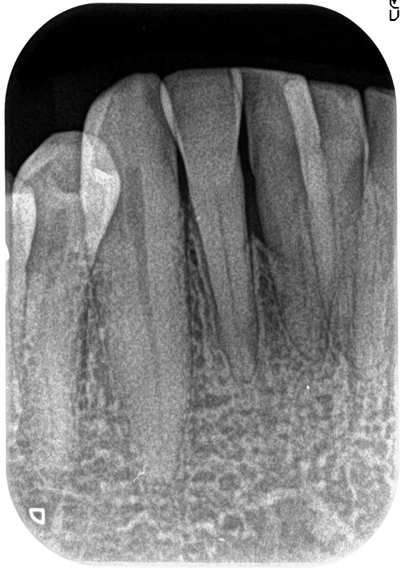

症例4右下1 リグロス(歯周組織再生剤)を使用

治療前

治療後(25ヶ月後)

主訴 右下中切歯からの排膿により来院。

まずは、約1ヶ月のブラッシング指導、噛み合わせの調整、プラークコントールが15%以下になったのを確認。

その後、フラップオペ(歯肉を開く)をし、縁下歯石の除去、歯周組織再生剤のリグロスを注入し、縫合。

約25ヶ月経過後、骨の高さも確認でき、クリアに皮質骨もできてきている。

費用 8万 (オペ・歯周組織再生剤を含む)